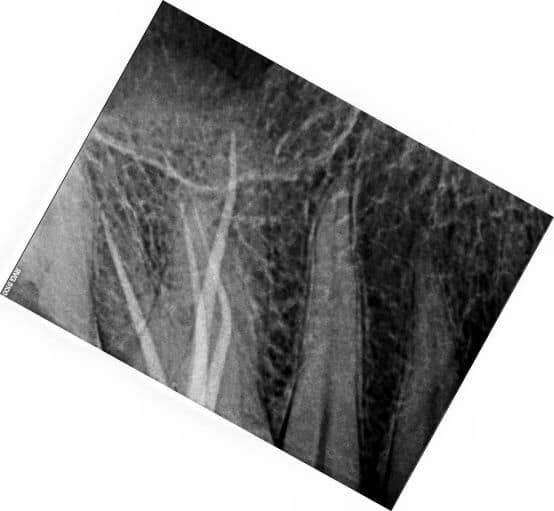

After shaping and cleaning the canal, a master cone of gutta-percha is placed into the canal. The dentist verifies the fit by taking a radiograph (X-ray) to ensure the cone reaches the full length of the canal and fits tightly against the walls.

Radiographs are taken during the filling process. The dentist examines these images to ensure the canal is fully occupied by the filling material, with no visible gaps or voids.

The fit and seal at the apical portion (tip of the root) are crucial to prevent bacteria from re-entering the canal. A snug apical seal is confirmed through radiographs and the tug-back test.

After obturation, a final radiograph is taken to confirm that the canal is uniformly filled with no gaps, indicating a successful snug fit.